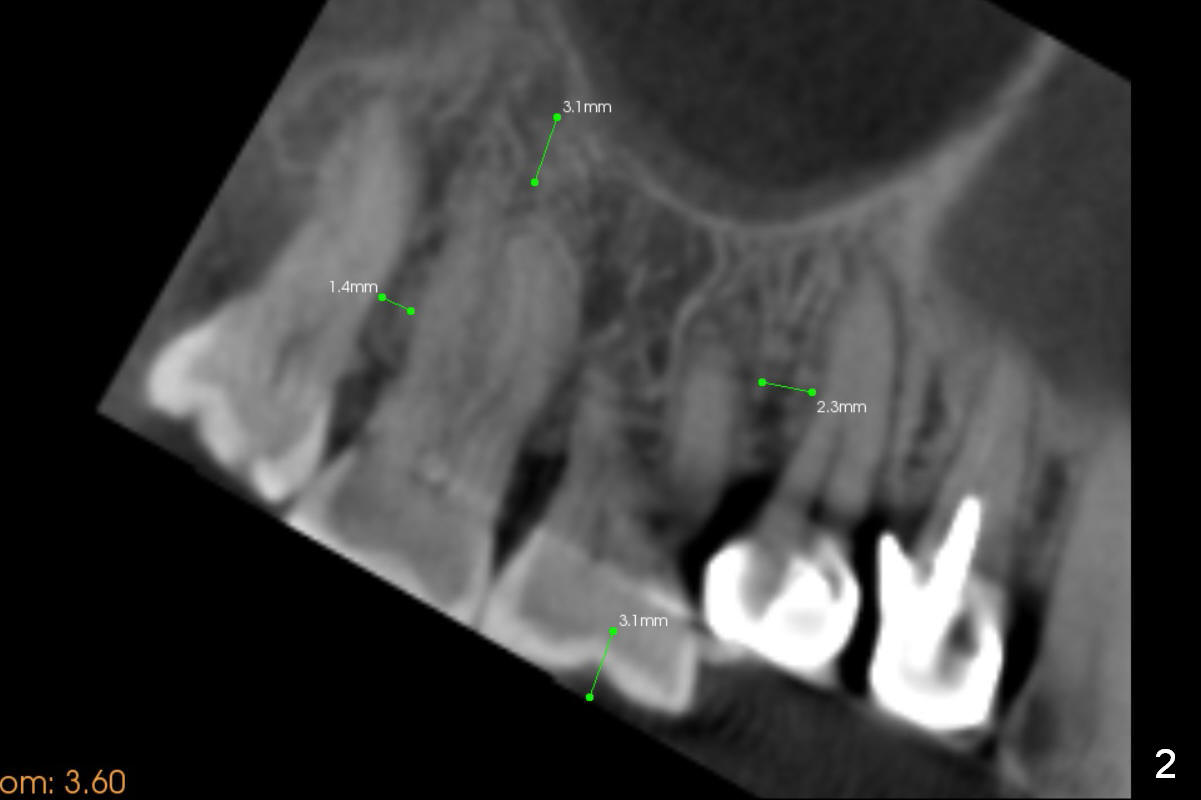

Orthodontic intrusion with mini-implants does not seem to work. When segmental brackets and bands are supplemented, the neighboring tooth (#14) becomes loose. CBCT 3 D and sagittal section show ~3 mm supraeruption of the teeth #2 and 3 (Fig.1,2). Diagnostic wax up demonstrates that the teeth #2 and 3 need to be intruded for 4 and 2 mm, respectively. Buccal gingival sulcus and anterior oblique incisions are shown in Fig.3 (red line). Osteotomy will be made with surgical fissure bur and chisels (Fig.4 red lines). The segment is down fractured (Fig.5 arrow). Apical bone is removed with acrylic bur and/surgical burs (Fig.6 cross lines). The segment is elevated and checked with a prefabricated splint out of diagnostic wax up. Insert a thicker orthodontic wire into brackets and bands buccally.